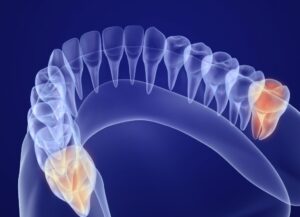

親知らずの抜歯

親知らずの抜歯においても、歯科用CT検査は重要です。

歯科用CT検査を行うことで、根と神経管の三次元的な位置関係を把握でき、抜歯の難易度や神経損傷のリスクを事前に評価することができます。